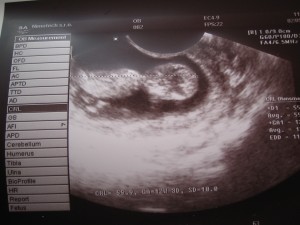

Moc ,moc tě zdravím.Tak včera jsme byli na velkém ultrazvuku.Termín porodu mám vypočítaný na 14.11.2008.Dnes začínám 13 týden.A jsem moc šťastná Kytičko.miminko bylo už celé vidět,mávalo na nás ručičkama,kopalo nožičkama,dělalo přemety.Viděli jsme jeho nosánek.Byl to pro mě a manžela nezapomenutelný zážitek.Máme ohromnou radost.Myslím,že to bude chlapeček.Paní doktorka mi řekla,že i když by to říkat neměla,považuje moje těhotenství za zázrak.Byla tak dojatá,že jsem zahlédla v jejich očích slzy,pořád mě objímala a cítila jsem z ní opravdovou radost,kterou z nás měla.Přiznala mi,že by ji ani ve snu nenapadlo,že by se to bez operace a hormonální léčby a dalších medikamentů obešlo.Cítila jsem z ní opravdovou radost. Moc ti za všechno děkuji kytičko,určitě dám vědět jak se nám vede.Máš nádhernou vnučku,ty její očička jen promluvit.Musím se k její fotce vracet.Je to přenádherné miminko ,takový malý andělíček.Jestli budeme mít holčičku tak chci aby to byla Karolínka...

Naše Karolínka už se má hezky k světu. Má dvě a půl kg navíc a umí se krásně hlasitě smát. Věř, že i Ty budeš mít veselé miminko. Moc moc děkuji za fotečku z ultrazvuku. Opravdu mám velkou radost z Tvého miminečka. Líbám Tebe i děťátko.